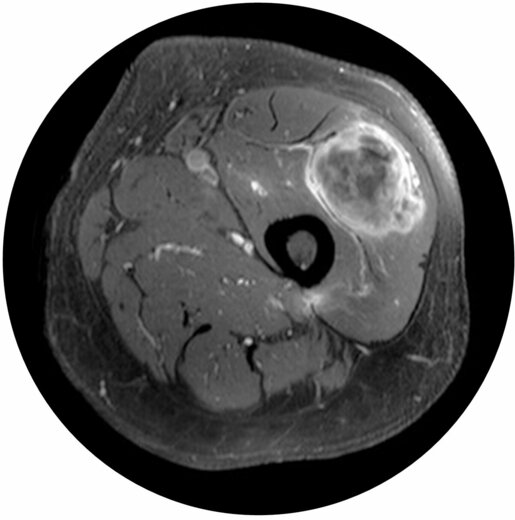

Auch Zellen der Weichgewebe (Fett, Muskeln, Sehen, Gefäße, Nerven) können entarten. Nach der genauen histologischen Zuordnung der Geschwulst durch die Biopsie kann individuell ein Behandlungsplan aufgestellt werden. Die vollständige operative Entfernung stellt die Hauptsäule der Tumortherapie dar. Durch eine Bestrahlung kann die Prognose verbessert werden.

Abb.: Weichgewebstumor in der Knieregion.